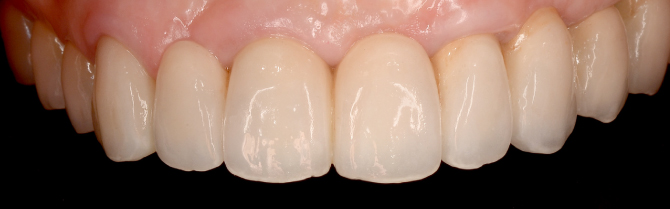

とびきり美しい上部構造

ただ治すのではなく、美しく治す。しかも、とびっきり美しく治すことにこだわっています。そのため、数々の賞を受賞する腕の良い歯科技工士と連携して歯をデザインしています。